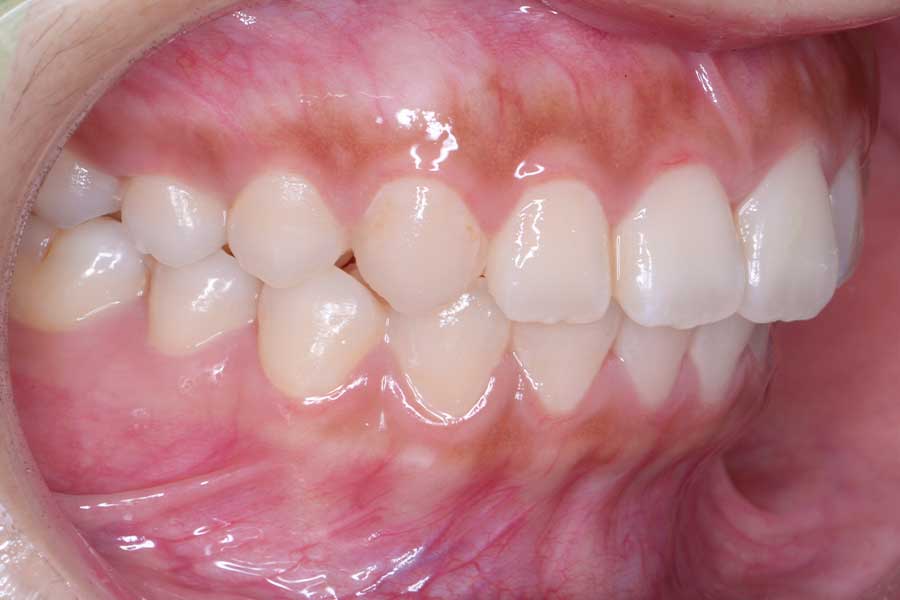

治療前

主訴 前歯の形と並びを良くしたい

治療内容 上下顎リンガル矯正(裏側矯正)